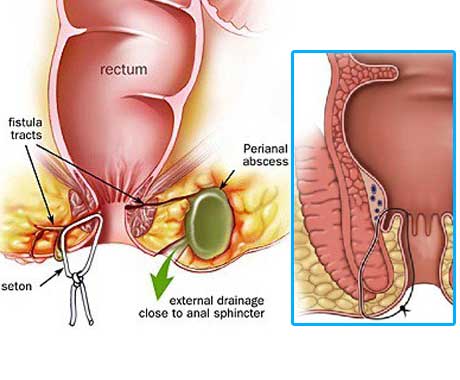

Overview

Package includes:

Days in hospital : 2 to 3 Days (For patient and one attendant)

Days in hotel : 7 Days (For patient and one attendant)

Room type in hospital : Shared

Room type in hotel : Private

Hotel category: Standard

Value added benefits of the Anal Fitsula:

Ø Doctor consultation charges

Ø Lab tests and diagnostic charges

Ø Room charges inside hospital during the procedure

Ø Surgeon Fee

Ø Nursing charges

Ø Hospital surgery suite charges

Ø Anesthesia charges

Ø Routine medicines and routine consumables (bandages, dressings etc.)

Ø Food and Beverages inside hospital stay for patient and one attendant.

Extra benefits:

ü Interpreter

ü Visa assistance

Ø Site tourism of the city

Ø Follow up with the doctor

Ø Airport pick up and drop

Ø Free online consultation with the doctor

Ø Priority appointments with the doctor

Ø Room upgrade from sharing to private